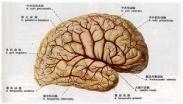

硬脑膜动静脉畸形

628健康网为您分享有关硬脑膜动静脉畸形的症状,硬脑膜动静脉畸形的治疗方法,硬脑膜动静脉畸形的预防知识,硬脑膜动静脉畸...

自发性蛛网膜下腔出血

628健康网为您分享有关自发性蛛网膜下腔出血的症状,自发性蛛网膜下腔出血的治疗方法,自发性蛛网膜下腔出血的预防知识...

头外伤

628健康网为您分享有关头外伤的症状,头外伤的治疗方法,头外伤的预防知识,头外伤的症状图片,头外伤吃什么药,头外伤怎么治...

急性硬脑膜下血肿

628健康网为您分享有关急性硬脑膜下血肿的症状,急性硬脑膜下血肿的治疗方法,急性硬脑膜下血肿的预防知识,急性硬脑膜下血...

慢性硬脑膜下血肿

628健康网为您分享有关慢性硬脑膜下血肿的症状,慢性硬脑膜下血肿的治疗方法,慢性硬脑膜下血肿的预防知识,慢性硬脑膜下血...

高血压性脑出血

628健康网为您分享有关高血压性脑出血的症状,高血压性脑出血的治疗方法,高血压性脑出血的预防知识,高血压性脑出血的症状...

非火器性颅脑开放伤

628健康网为您分享有关非火器性颅脑开放伤的症状,非火器性颅脑开放伤的治疗方法,非火器性颅脑开放伤的预防知识,非火器性...

颅后窝血肿

628健康网为您分享有关颅后窝血肿的症状,颅后窝血肿的治疗方法,颅后窝血肿的预防知识,颅后窝血肿的症状图片,颅后窝血肿...

急性脑内血肿

628健康网为您分享有关急性脑内血肿的症状,急性脑内血肿的治疗方法,急性脑内血肿的预防知识,急性脑内血肿的症状图片,急...